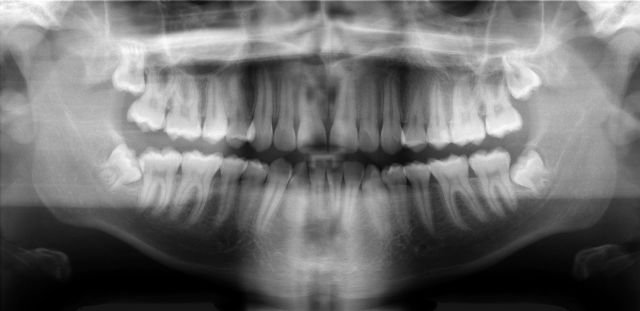

De plus, avec la reconnaissance de caractère (OCR), même non combinée à l'intelligence artificielle, on trouve des données dans n'importe quelle pièce, y compris dans les radiographies où sont incrustées les données personnelles : Name, first name,